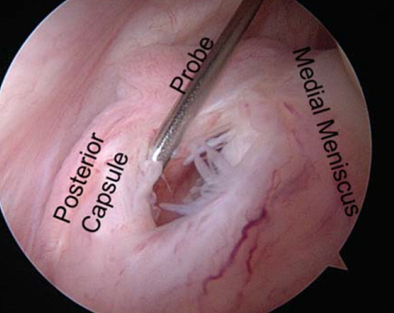

Figure 1

A ramp lesion is a tear or disruption in the peripheral meniscocapsular attachments in the posterior horn of the meniscus (Figure 1). They are common with ACL injuries. It's reported that they are present in around 10-40% of all ACL tears. The posterior horn of the medial meniscus is confluent with the joint capsule. Sometimes, instead of tearing the posterior horn of the medial meniscus, patients will instead tear the capsular attachment to the meniscus. There are two separate ligaments called the meniscotibial and the meniscocapsular ligaments.